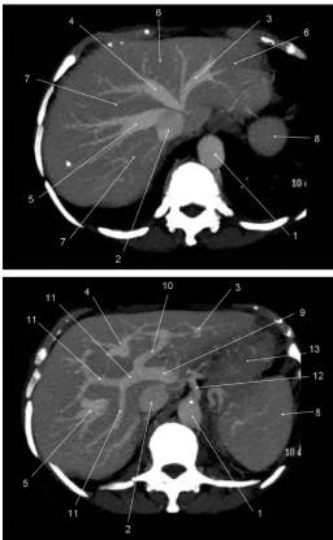

Fig. 2.1 Coupes tomodensitométriques axiales du foie après injection de produit de contraste iodé reconstruites en MIP (Maximum Intensity Projection) de 3 cm d’épaisseur, faisant ressortir préférentiellement les vaisseaux opacifiés situés dans toute l’épaisseur de coupe.

1. Aorte abdominale. 2. Veine cave inférieure. 3. Veine hépatique gauche. 4. Veine hépatique médiane. 5. Veine hépatique droite. 6. Lobe gauche du foie. 7. Lobe droit du foie. 8. Rate. 9. Veine porte. 10. Branche porte gauche. 11. Branche porte droite. 12. Tronc cœliaque. 13. Estomac.

Fig. 2.2 Coupes axiales de 2 mm d’épaisseur sur l’étage sus-mésocolique.

1. Aorte abdominale. 2. Veine cave inférieure. 7. Lobe droit du foie. 8. Rate. 13. Estomac. 14. Artère mésentérique supérieure. 15. Veine mésentérique supérieure. 16. Vésicule biliaire. 17. Rein droit. 18. Rein gauche. 19. Pancréas. 20. Glande surrénale gauche. 21 et 23. Côlon transverse. 22. Côlon descendant. 24. Côlon ascendant. 25. Partie horizontale du duodénum. 26. Jéjunum.